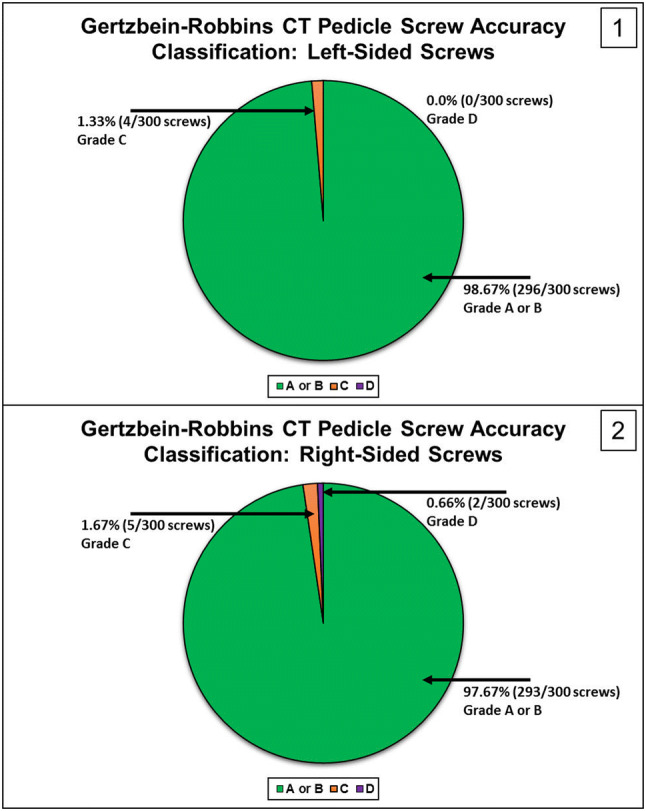

Based on the GRS CT-based grading for the left side screws, 98.67% (296/300) were graded A or B, 1.33% (4/300) screws were graded C, and 0% (0/300) screws were graded D (Fig. 2). Based on the GRS CT-based grading for the right-side screws, 97.67% (293/300) were graded A or B, 1.67% (5/300) screws were graded C, and 0.66% (2/300) screws were graded D (Fig. 3). Using a Chi square test, there were no significant differences between the left and right sides in screw accuracy (p > 0.05).

Fig. 2.

Fig. 3.

Gertzbein-Robbins CT pedicle screw accuracy classification for left (1) and right-sided (2) screws